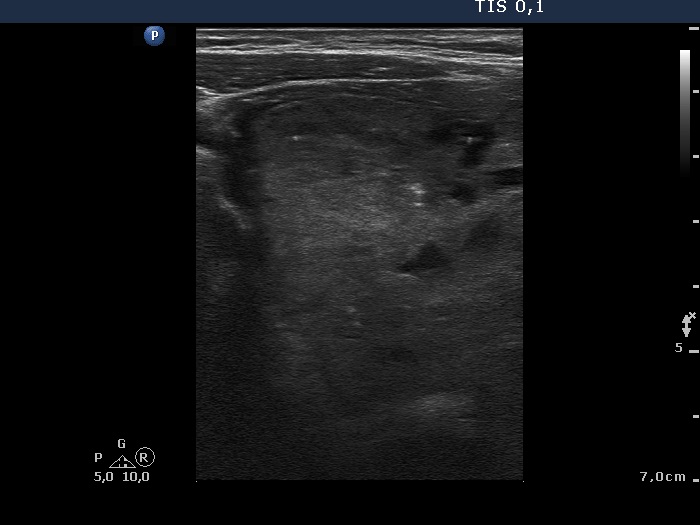

Ultrasonography. The right thyroid was composed of multiple discrete lesions with different echogenicities. The lobe was extremely enlarged with the dimension of 55x65 xminimum 120 mm (width, depth, and length, respectively) and spread retotracheal and substernal. The lower pole of the lobe could not be visualized while swallowing. The left thyroid was normal-sized and contained several hypoechogenic lesions. There was a moderately hypoechogenic nodule in the right lobe. The lesion presented neither halo nor perinodular blood flow.